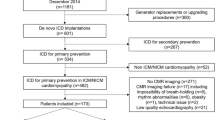

The study was conducted at Medisch Spectrum Twente, Enschede, the Netherlands. A consecutive series of patients with prior MI, who received an ICD for primary or secondary prevention following current guidelines of the Dutch (NVVC) and European society of Cardiology (ESC) in which the LVEF was determined based on echocardiographic findings, was assessed. The referring physicians had no access to the CMR report before defining therapeutic management. Prior to ICD implantation, these patients were referred for CMR to assess left ventricular (LV) dimension and function, and after intravenous injection of gadolinium, characterization of the infarcted tissue. According to current guidelines, the patients who received ICD treatment for primary prevention had an indication based on a LVEF ≤ 35 % (majority of patients) or the presence of spontaneous ventricular tachycardia, even with a somewhat more preserved LV function. Patients were only included in the study if the MI occurred at least 1 month prior to CMR (according to the definition of a healed MI [19] and a positive infarct pattern on CE imaging was found. The study was approved by the local ethics committee and informed consent was obtained.

In this study, 95 patients (64 ± 10 years old; 79 men) with a median of 141 (1–434) months after MI were examined. A total of 66 patients received an ICD for primary prevention and 29 patients for secondary prevention. Indication for secondary prevention by ICD implantation was (1) SCD in 14 patients (48 %) or (2) VT episodes in 15 patients (52 %). Time between events and ICD implantation was on average 2 weeks (median). (25th percentile 1 week, 50th percentile 2 weeks, 75th percentile weeks). In general, ICD implantation was performed shortly after CE-CMR assessment; the average (median) within 1 week, the 75th percentile within 1 week and the 90th percentile within 5.4 weeks. Demographics and baseline characteristics did not differ between groups except for diuretic usage (80 % vs. 45 %; P < 0.01). Patient demographics are presented in Table 1, which also shows a subgroup of patients with LVEF ≤ 35 %.